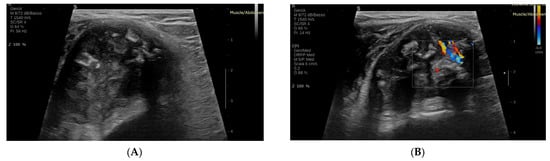

Benign tumors typically demonstrate minimal or absent vascularity, with vessels arranged peripherally or in an organized configuration (Figure 1). The peak systolic velocity (PSV), which refers to the highest speed of blood flow during the heart’s contraction phase (systole), measured in centimeters per second (cm/s), is generally low (<30 cm/s), and the resistive index (RI), a ratio that compares the PSV to the end-diastolic velocity (the speed of blood flow during the heart’s relaxation phase), indicating the level of vascular resistance, remains below 0.7, indicating low arterial resistance and limited blood flow activity [19].

Figure 1. Conventional US of a benign STT (Chondroma) (A): B-mode US image; (B): color Doppler ultrasound image.